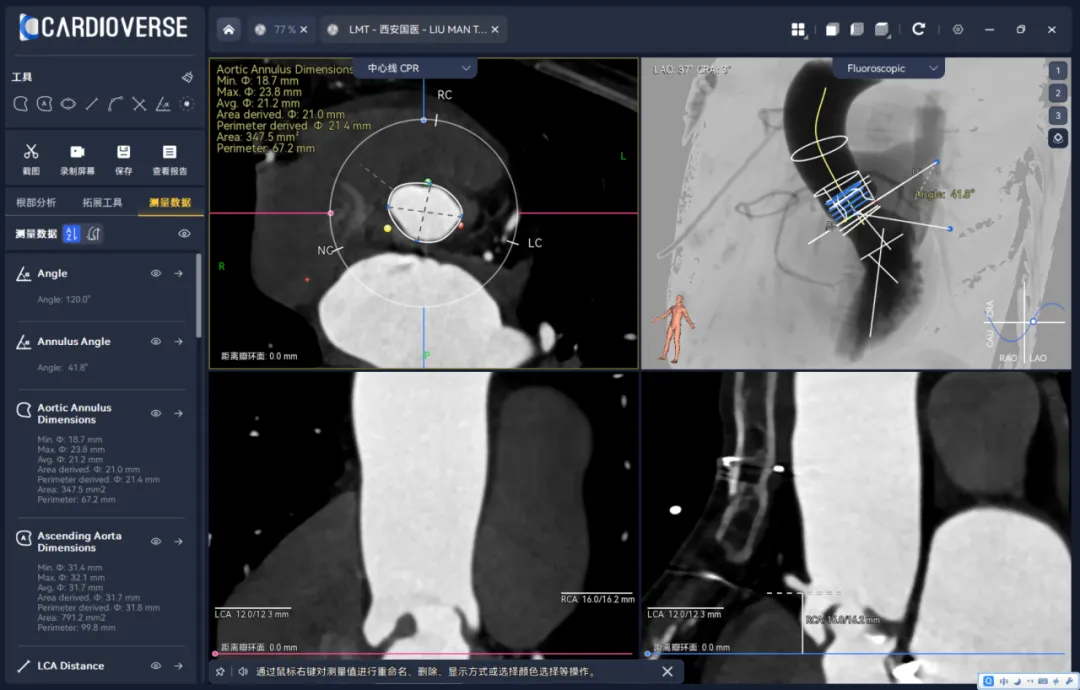

图1:自动分析演示(Tavigator™平台、由吴永健教授团队与拓微摹心数据科技(南京)有限公司合作)

• 核心产品与功能:核心产品为3mensio Structural Heart 工作站,分为结构心与血管两大模块,其中结构心模块覆盖 TAVR/TMVR/PPVI/LAAO 等全术式的术前规划,核心功能包括:主动脉根部 / 二尖瓣 / 左心耳等结构的自动化分割与精准测量、虚拟瓣膜植入、钙化积分评估、入路血管分析,支持非增强扫描融合分析。

技术优势:操作流程标准化,测量结果被全球主流瓣膜厂商作为金标准参考,支持手动调整与自动化功能结合,临床适配性强;

小编点评:在术前分析测量领域,3mensio的界面是最好的,但因为软件自动拉伸各截面,准确性比手动测量的软件稍差,部分医院:如华西喜欢使用Fluoro CT测量。